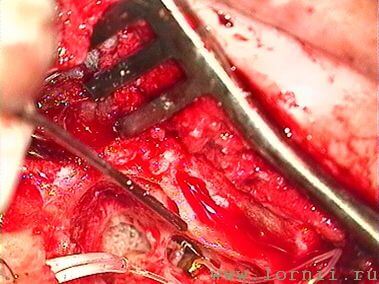

У пациентов с аномалией развития уха и после радикальной операции катушка импланта была установлена в круглое окно (рис. 13, 15, 16). Для этого крепление катушки подворачивали (рис. 14). Далее укладывали фасцию височной мышцы в нишу окна улитки (рис. 15), затем на фасцию устанавливали катушку импланта и подворачивали края фасции. Фиксация конструкции обеспечивалась полоской аутохряща из ушной раковины пациентки (рис. 16).